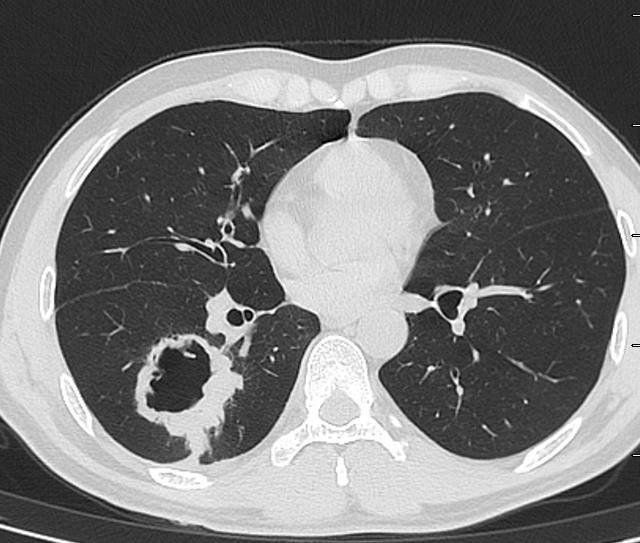

CT发现右肺下叶一大个空洞。

图01

这个空洞,是个典型的肺鳞癌。根本就没有必要放个引流管。

首先,患者没有明显的感染症状!其次,这个空洞没有气液平,也不像肺脓肿。最后,这个空洞乱糟糟的,有些地方壁厚,有些地方壁薄,空洞里面凹凸不平,空洞周围边界清晰,没有炎症反应引起的模糊阴影。外加患者是中年人,基本上就是肺鳞癌。